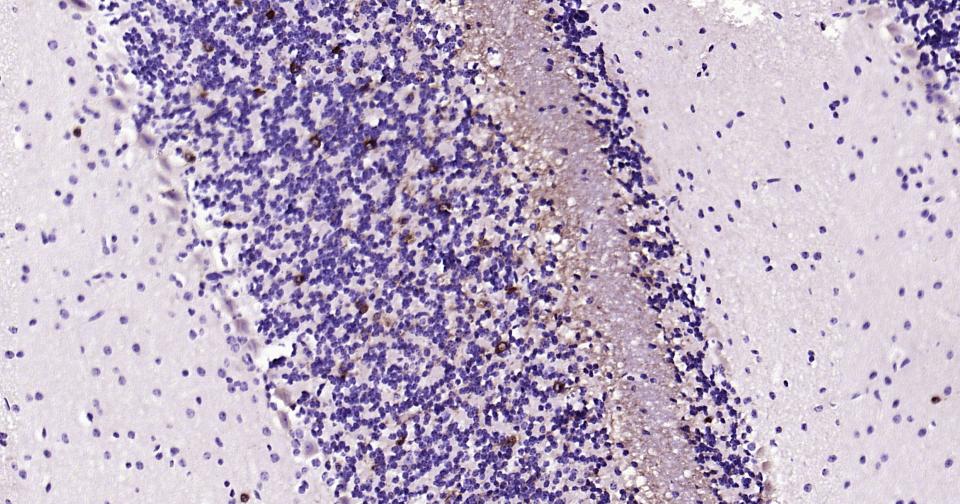

神经细胞标志物

(NMDAR1)N-甲基-D-天门冬氨酸受体(NMDAR)是兴奋性氨基酸受体亚型之一,是由NMDAR1与不同的NMDAR2亚基组成的异聚体。

近年实验研究发现,许多NMDAR拮抗药均具有镇痛活性,表明NMDAR在痛觉传递中具有重要作用,这为新型镇痛药的研究开发提供了新的作用靶点。

The protein encoded by this gene is a critical subunit of N-methyl-D-aspartate receptors, members of the glutamate receptor channel superfamily which are heteromeric protein complexes with multiple subunits arranged to form a ligand-gated ion channel. These subunits play a key role in the plasticity of synapses, which is believed to underlie memory and learning. Cell-specific factors are thought to control expression of different isoforms, possibly contributing to the functional diversity of the subunits. Alternatively spliced transcript variants have been described. [provided by RefSeq, Jul 2008]

| IHC-P | Human, Mouse, Rat | 1:100-500 | |